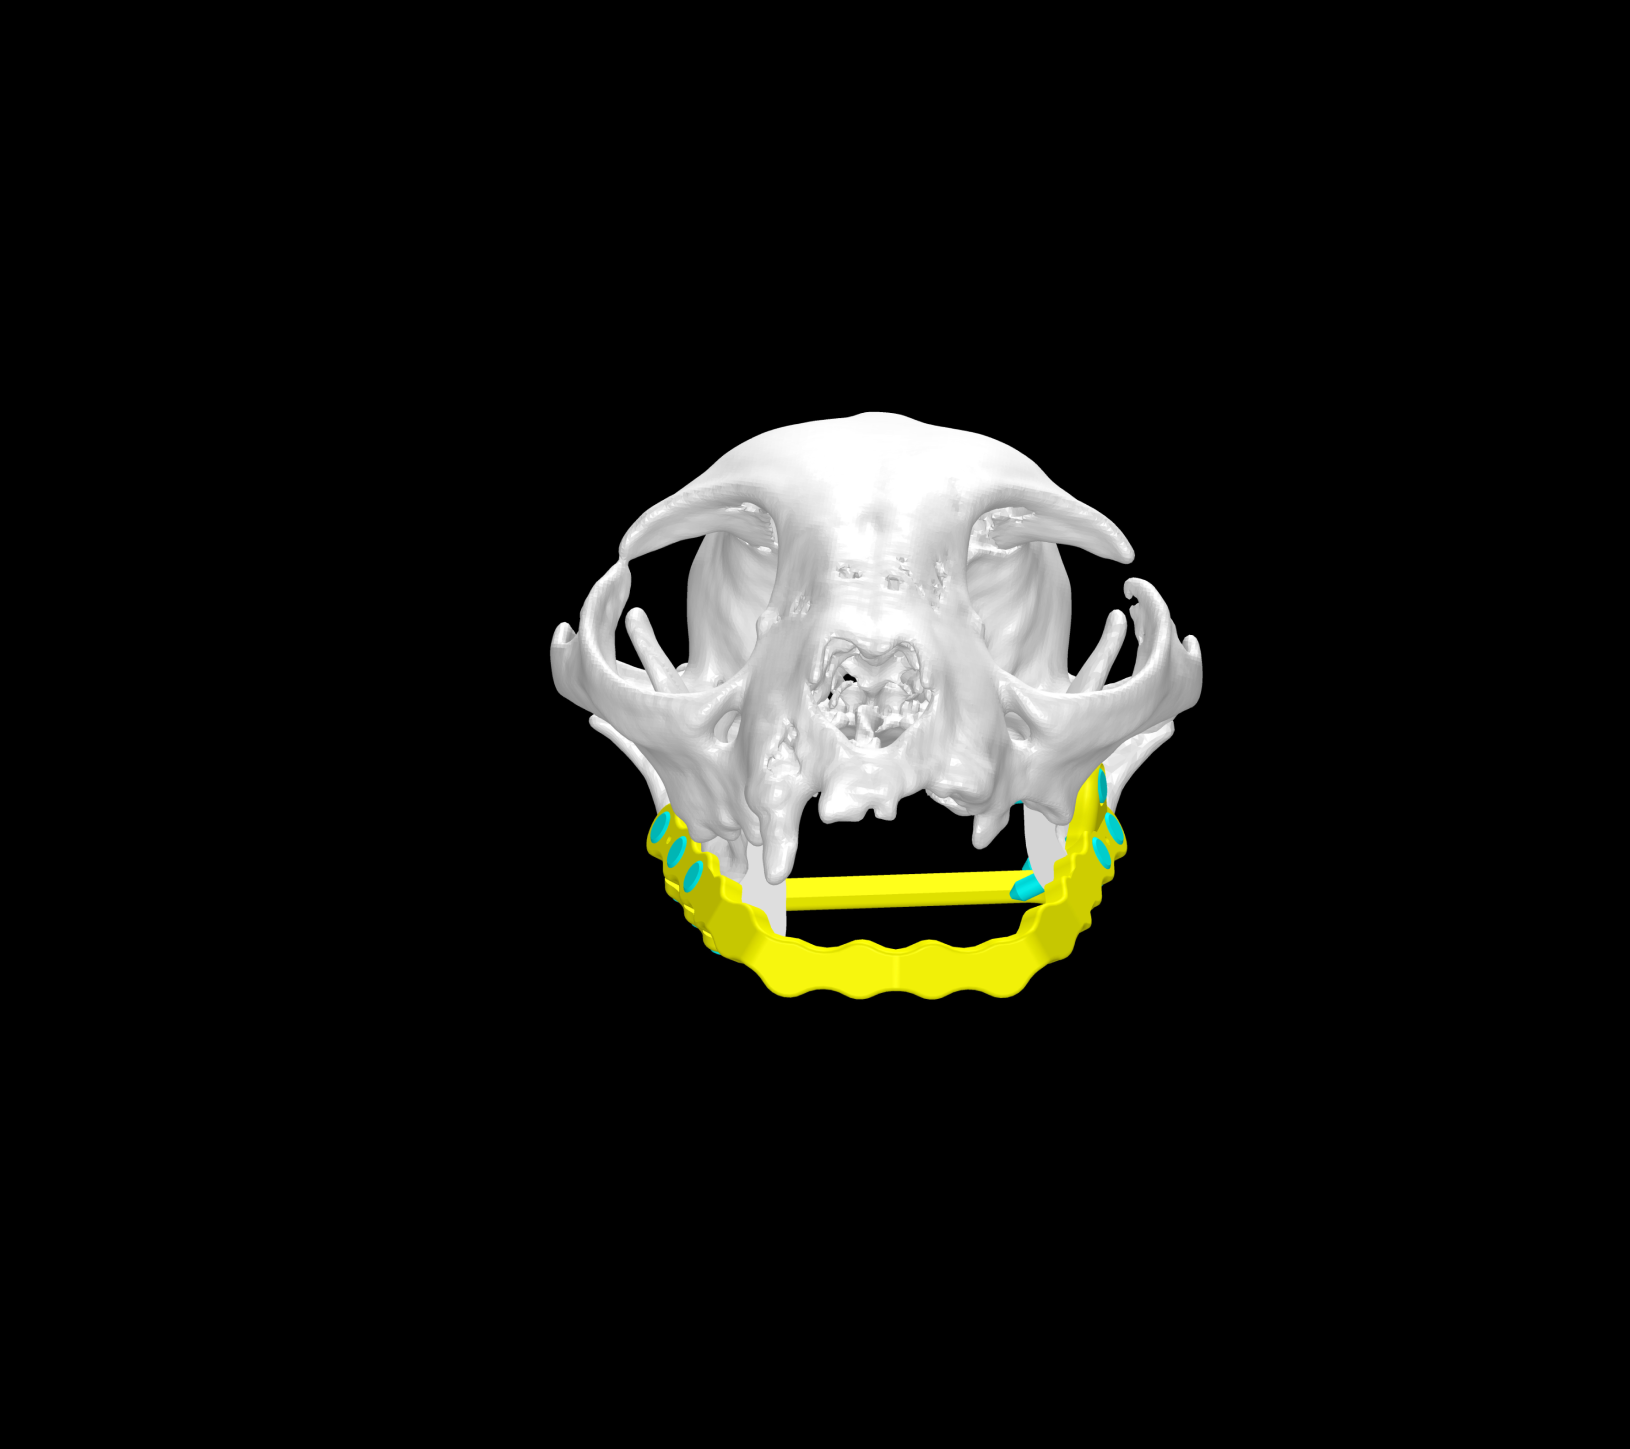

Esto se consigue gracias a los avances en la tecnología de fabricación, como la impresión 3D. Con esta tecnología se pueden crear implantes personalizados tanto en acero quirúrgico como en titanio a partir de imágenes médicas de tomografías computerizadas (TC) o resonancias magnéticas (RM).

Además disponemos la posibilidad de conseguir una fabricación rápida y de calidad de estos implantes gracias a trabajar de la mano con bioingenieros.